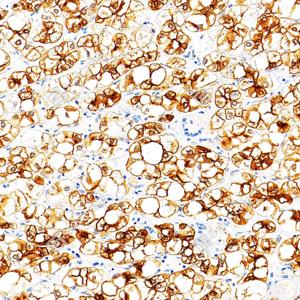

IHC检测Cytokeratin 18蛋白(货号 GB15232). 样品: 人子宫内膜癌, 4%多聚甲醛 (货号G1101) 固定12-24小时. 抗原修复: 柠檬酸抗原修复液(干粉, pH 6.0) (G1201), 高压锅均匀喷气计时2分钟. —抗: 1: 500稀释, 4℃ 孵育过夜. 二抗: S-vision免疫组化多聚二抗(山羊抗小鼠), 即用型(货号G1301), 室温孵育20分钟. |